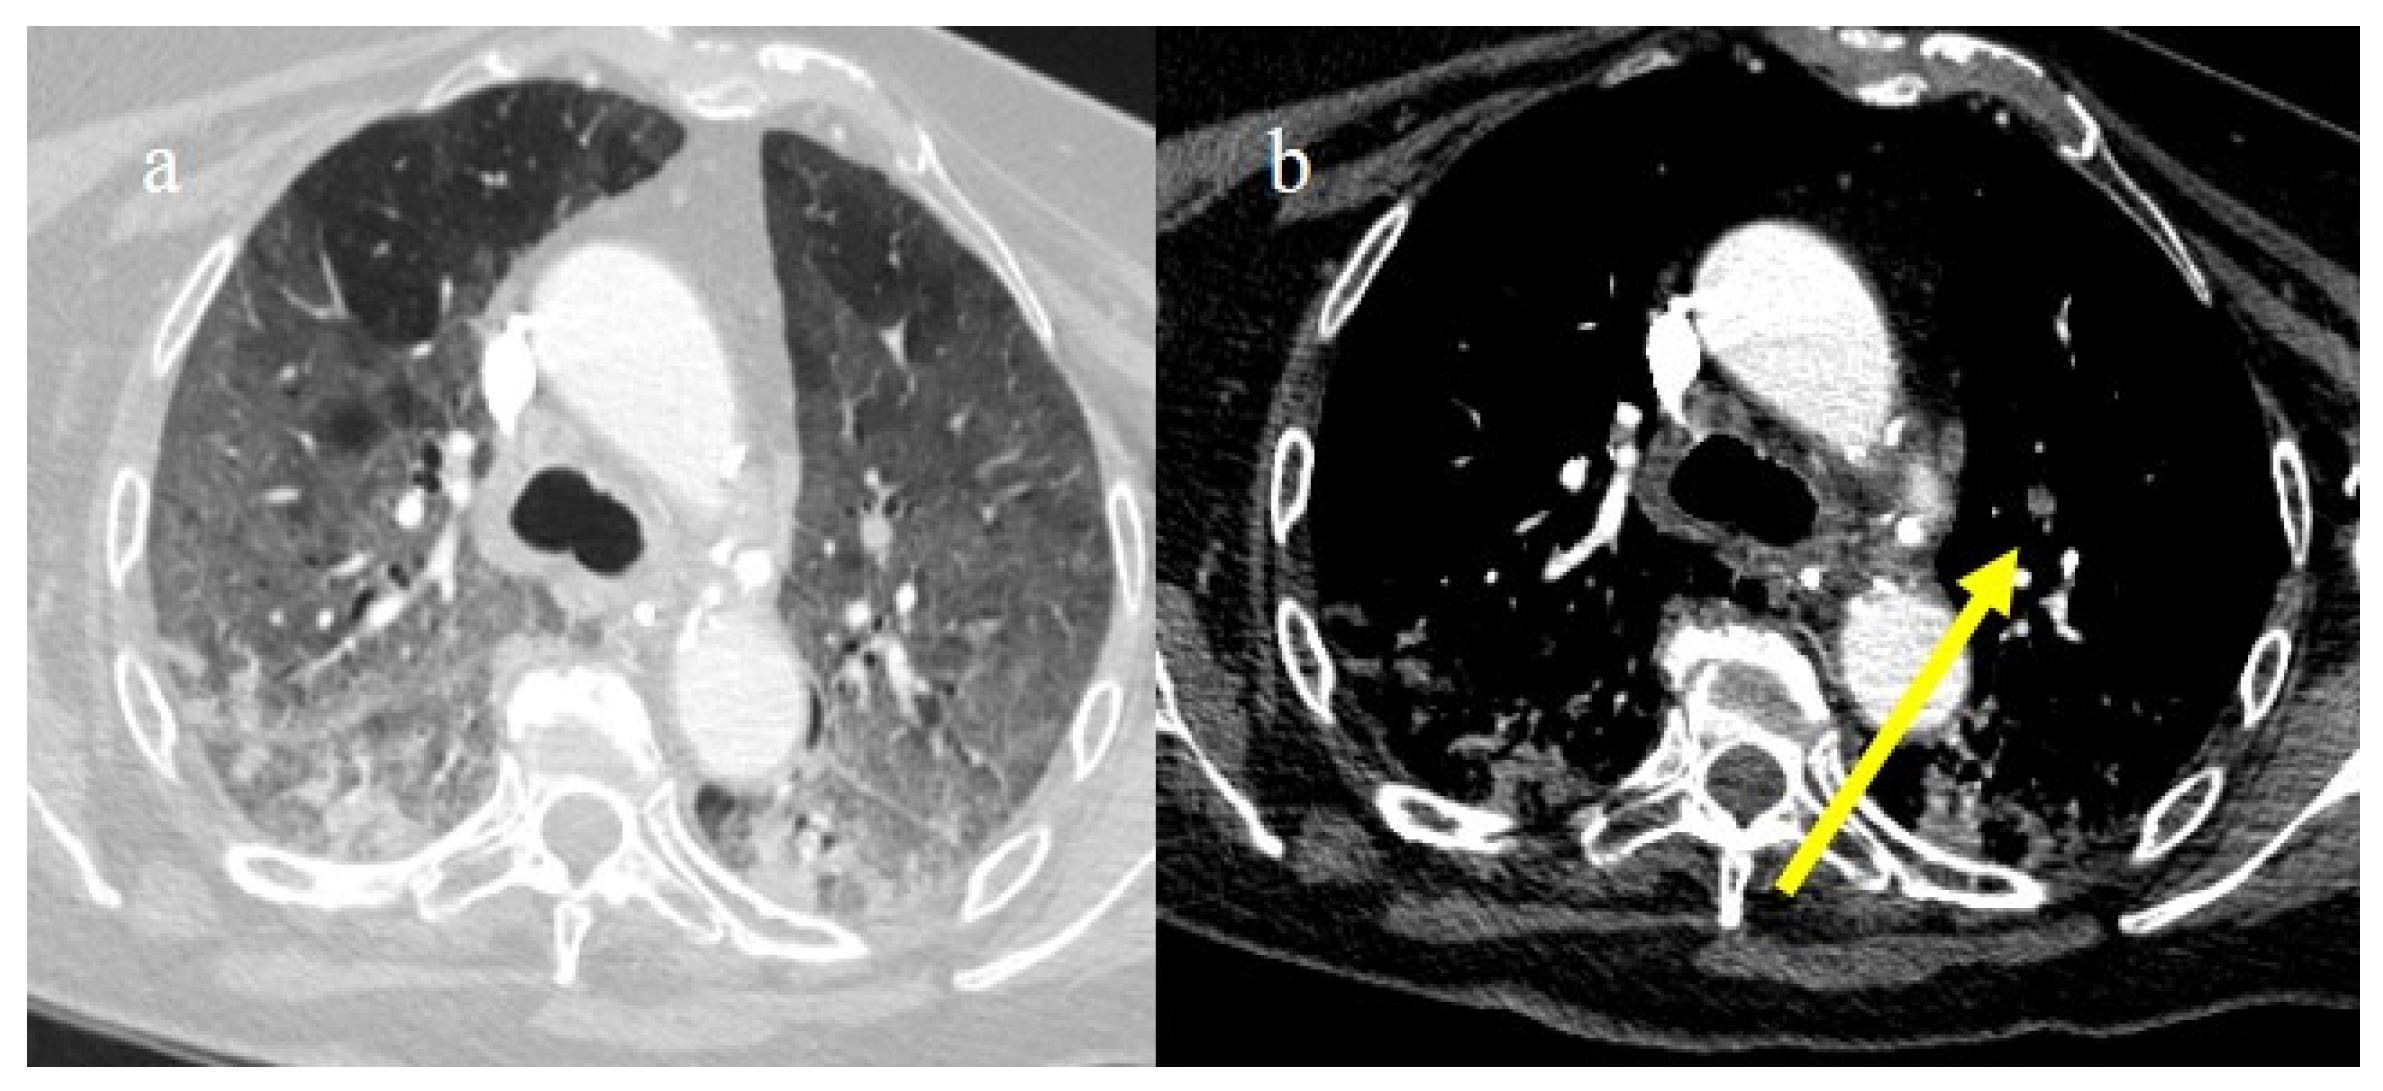

In the early phase of the pandemic, the important role of a prothrombotic state in the virus infection became rapidly clear, with evidence of dilated pulmonary vasculature in regions affected by pneumonia according to CT and a high incidence of pulmonary thromboembolism (PE), according to CT pulmonary angiography (CTPA) [12,133,134,135,136]. Nevertheless, during the first phase of the pandemic, complete autopsy studies were rarely performed because of the risk of infection, and PE could have been underestimated [133,134,135]. However, the first autopsies highlighted the importance of thromboembolic events in COVID-19, suggesting de novo coagulopathy in patients with COVID-19, and autopsy studies reported the presence of microscopic thrombi formation in the lung histology [12,133,134,135,136]. Several authors found a higher incidence of pulmonary embolism with or without deep venous thrombosis in COVID-19 patients with no history of venous thromboembolism (VTE). Thrombotic events in hospitalized COVID-19 patients were observed despite VTE prophylaxis [10,12,136,137,138,139]. A recent meta-analysis reported that autoptic findings of acute PE in COVID-19 patients were present in about 30% of the subjects [10]. Radiology case reviews reported high rates of PE, ranging from 17% and 50%, especially in patients who were admitted to the ICU [133] (Figure 20, Figure 21 and Figure 22).

Figure 20.

Chest CT of a 79-year-old patient in ICU during the second pandemic wave (October 2020) with severe COVID-19 pneumonia with CT-SS OF 20/25 with diffuse GGOs and initial consolidations as shown in image (a). On the CT pulmonary angiogram, a thrombosis was found in the anterior pulmonary segmentary artery of the left superior lobe, as shown in the image (b) (yellow arrow).

Figure 21.

Chest CT of a 70-year-old patient in ICU in the second pandemic wave (November 2020) with severe COVID-19 pneumonia with CT-SS OF 23/25 with diffuse consolidations in the inferior lobe in image (a). The CT pulmonary angiogram showed that lung thromboembolism was present; in image (b), a thrombosis in the lobar artery branch for the left inferior lobe (yellow arrow) was described.

Figure 22.

Chest CT of an 81-year-old patient in ICU during the transition period of Delta-Omicron variant (January 2022) (vaccination status unknown, probably concerns a breakthrough infection) with severe COVID-19 pneumonia with CT-SS of 23/25 with diffuse interstitial thickness and consolidations in the superior lobes, as visualized in image (a). The CT pulmonary angiogram showed thrombosis in the distal portion of the left pulmonary artery (yellow arrow) in image (b); severe pneumonia with consolidations in the apical segment of inferior lobes in image (c) and thrombosis in a segmentary branch (yellow arrow) in image (d).

This increased prevalence occurred despite a simultaneous decrease in the overall number of CTPA exams performed during the pandemic. Recently, Wusmuller et al. [133] showed that the prevalence of PE increased significantly as reported by CTPA exams during the first wave of the COVID-19 pandemic, despite the reduction in the number of radiological examinations carried out due to lockdown measures. Segmental arteries were generally the most common location for PE [24,140] (Figure 23).

Figure 23.

CT pulmonary angiogram of an 80-year-old patient during the second wave (December 2020) with multiple lung thromboembolism mainly located in the segmentary pulmonary artery branches; in image (a) some defect of opacification compatible with thrombi in some subsegmental branches (yellow arrow) of left superior lobes and in the segmentary branch for the apicodorsal segment (yellow arrow) in image (b); in image (c) lung thromboembolism in the lobar branch for the middle lobe (yellow arrow); and in image (d) in a subsegmental branch in the left inferior lobe (yellow arrow).